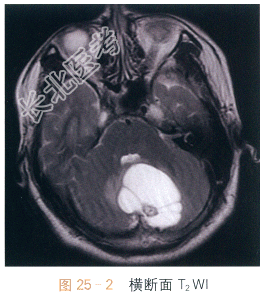

影像学资料如图25-1~图25-4所示。

读片分析:头颅横断面T₁WI示小脑半球囊性占位,呈低信号影,边界清晰,边缘光整,内可见附壁结节,呈等低信号影,第四脑室受压改变;横断面T₂WI囊液呈脑脊液样高信号影;增强扫描可见附壁结节明显强化。结合病史,患者考虑为血管母细胞瘤。